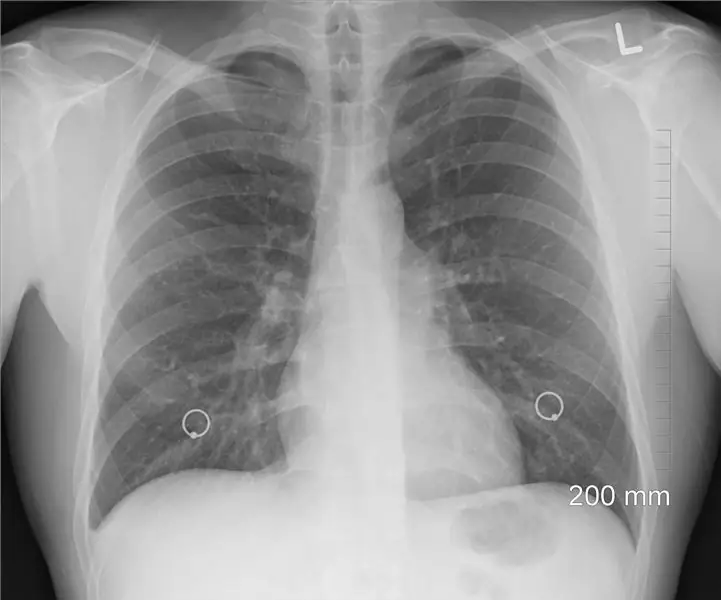

Одно легкое

Конечно, если в наших телах есть два чего-то, значит, нам нужно два, верно? Ну нет. Слейт отмечает, что жизнь с одним легким или, может быть, с половиной легких не так уж сильно отличается от двух целых. «Можно предположить, что потеря одного из двух легких уменьшит дыхательную способность вдвое, но это не так, потому что человеческое тело имеет значительные резервы». Кто-то, кому удалили легкое хирургическим путем, сохраняет от 70 до 80 процентов своей дыхательной функции: «Выжившее легкое вскоре расширяется, чтобы компенсировать потерю своего партнера, и регулярные упражнения ускоряют этот процесс». Если один из этих органов дыхания будет удален, это не повлияет на выполнение физических упражнений.

Одним из основных побочных эффектов является однобокость, потому что при отсутствии легкого остается пустота. «Сундуки слегка опускаются; сердце, печень и оставшееся легкое смещаются к пустоте; и жидкость заполняет оставшуюся часть полости. В конце концов, эта жидкость желатинизируется и превращается в белковую слизь. В результате всего этого движения позвоночник может изгибаться на 15-30 градусов в сторону без легких, что часто заметно для наблюдателя, стоящего сзади ». В некоторых случаях односторонность может затруднять дыхание.